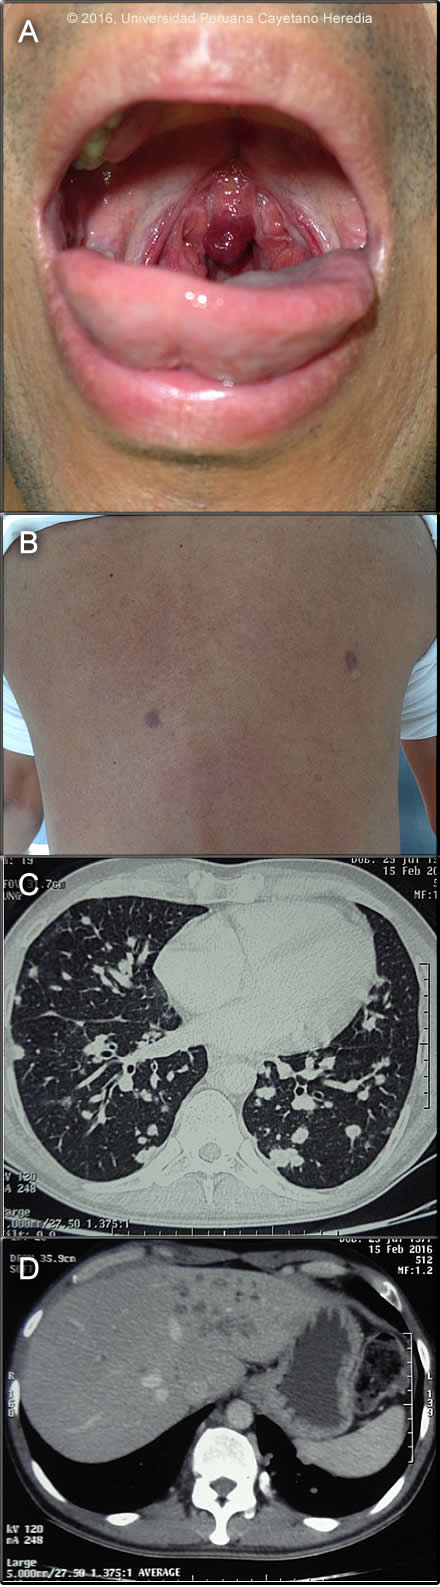

Epidemiology: Born and lives in Lima and is an accountant. No known TB contact history. Travel to Cuzco 3 months before re-presentation. Physical Examination: T 36.5. RR 14; pulse 76; BP 100/64; BMI 23.17. HEENT: violaceous infiltrative lesion of the uvula (Image A), 11 papular, violaceous lesions located on the trunk and extremities (Image B). No lymphadenopathy. Chest: few rales in both lungs. Abdomen: no hepatosplenomegaly. Laboratory Examination (on admission) and Imaging:CD4 cell count: 34 cells/mm3 ; viral load is pending. Hemoglobin: 10.7, Hematocrit: 32%, WBC: 4.78K, Neutrophils:59%, Lymphocytes: 32, Platelets: 282K. Glucose: 97, Creatinine: 0.9; AST: 31, ALT: 37. Total Protein: 6.9. Albumin: 4, Total Bilirrubin: 0.4, Alkaline Phosphatase: 331 (elevated). Sputum AFB: negative x 3. AFB culture (MGIT): negative. HTLV1: not reactive; RPR not reactive. CT scan of the chest and abdomen are shown (Images C & D). CEA 1.79 (normal)

Diagnosis:Kaposi`s sarcoma (KS due to HHV8); HIV associated.

![]() Discussion: Biopsy of a skin lesion showed (Image E): microvascular proliferation (varying vessel shape and size with vascular congestion and RBC extravasation (black arrows); spindle cells (sarcomatoid cells) with pale eosinophilic cytoplasm and oval elongated nuclei (white arrows); occasional mitotic figures (arrow head). These 3 findings together are diagnostic of KS. CT scan of the chest (Image C) was read as showing multiple nodular lesions of different sizes located in both lungs and the CT scan of the abdomen (Image D) as showing hypondense lesions of the liver. GI endoscopy and colonscopy showed multiple violaceous lesions in the small and large intestine (images not available). Bronchoscpy did not show any endobronchial lesions and KOH, Grocott and ZN of the BAL were negative as were MGIT cultures for MTB and cultures for other mycobacteria. Latex agglutination test Cryptococcus was negative and histoplasma and paracoccidiodomycis immunodiffusion were negative. Culture for nocardia was negative. The differential diagnosis of the skin lesions in this patient includes mainly bacillary angiomatosis due to Bartonella; the biopsy helps in distnguishing these conditions, and a Waathin-Starry stain would indentify clumps of bacteria in bacillary angiomatosis. The differential diagnosis of pulmonary nodules in patients with HIV is broad and includes TBC, nocardia which is usually associated with skin lesions that look like nodules and abscesses, and fungal pathogens including histoplasma, paracoccidiodomycosis and cryptococcus Pneumocystosis rarely presents with nodules. Cancer including KS (the most likely), lymphoma, and metastatic cancer should also be considered. Kaposi’s sarcoma is caused by HHV-8 (human herpes virus 8) and was first described in Africa in the pre-HIV era. It is the most common HIV associated malignancy including in Latin America (J Acquir Immune Defic Syndr. 2011 April 15; 56(5): 467–473. doi:10.1097/QAI.0b013e31820bb1c3) and in some African countries with high HIV rates it is the most common malignancy in men. For unclear reasons though, it is uncommon in Asia. HHV-8 transmission routes are not totally clear and both sexual and horizontal nonsexual (mother to child; between siblings) HHV-8 transmission routes have been reported. Due to low general seroprevalence of HHV-8 in the population in developed countries and early initiation of anti-retroviral therapy, HIV-related KS is an infrequent condition in developed countries. Currently, KS is more commonly reported from developing countries than developed countries. HIV-infection is an important risk factor for developing KS in developing countries. HIV-infection is associated with an increased HHV-8 sero-prevalence in all population groups examined. Overall, HIV-positive persons are more likely to be HHV-8 seropositive than HIV-negative persons and the association is strongest in MSM, patients with hemophilia, and children (Int. J. Cancer: 138, 45–54, 2016). Co-infection with HIV and HHV8 is more frequent in males (reasons unclear), and is usually seen in severely immunosupressed patients, the lower the CD4 the higher the risk. Patients typically have a CD4< 200 cells/mm3 and history of an opportunistic infection such as pneumocystis. In patients who present with limited disease there is no indication to start chemotherapy; these patients will benefit from HAART (any regimen) alone (AIDS Reviews 7: 13-21, 2005). Clinically, this is a case of advanced poor-risk KS based on three criteria: 1) Tumor, T1 stage; 2) extensive disease that involves not only the skin but also mucosal membranes; 3) involvement of other non-lymph node viscera involved (lungs, GI tract and liver). Treatment of KS in HIV-infected patients depends on the stage of the tumor and number of skin lesions (this patient had less than 50) and presence of symptomatic disease. Considering the extensive involvement in this case and despite of the scarcity of symptoms chemotherapy was offered. 5-year survival in T1 disease has been approximated as 80% with HAART and chemotherapy but the extensive pulmonary disease in our patient speaks to a poorer prognosis in our experience. The standard of care in the developed world is liposomal anthracyclines (doxorubicin or daunorubicin), but these drugs are not available in most of the developing world (Cochrane Database of Systematic Reviews 2014, Issue 9. Art. No.: CD003256. DOI: 10.1002/14651858.CD003256.pub2). Alternatives are IV combination of vincristine + vimblastine, IV paclitazel or oral etoposide. The patient was started on paclitazel, as per local protocol, and ART (Atripla). |